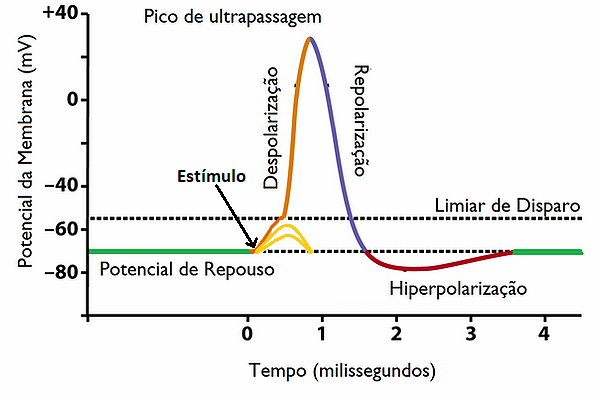

Olhando para Figura 2 vemos alguns aspectos importantes:

- O potencial de ação necessita de um estímulo mínimo (limiar) para ser ativado, abaixo desse valor o estímulo decai como em uma célula não excitável;

- Acima desse limiar a célula segue o principio de "Tudo ou Nada", ou seja, assume o valor máximo possivel dentro de sua capacidade, independente do estímulo aplicado;

- A etapa de despolarização (crescimento) é brusca e varia mais rapidamente que a repolarização (decaimento);

- O período que contém a repolarização e hiperpolarização da membrana é chamado período refratário, e se caracteriza por não permitir que ocorra nenhum disparo até que a membrana atinja o potencial de repouso.

Na figura 10 vemos a evolução temporal do potencial elétrico em um ponto da membrana do axônio () quando excitado acima do limiar de potencial. Note que a curva do PA é muito semelhante àquela da na Figura 2, apresentando vários dos aspectos característicos, como a assimetria entre os períodos de polarização (ascensão rápida) e repolarização (decaimento mais lento) e um período refratário, onde o potencial lentamente se recupera em direção do PR. Podemos assim entender a escolha dos valores dos parâmetros e , que controlam a velocidade de crescimento da variável de recuperação (assim como se pode ver na equação (3)). Experimentalmente, sabemos que o período refratário é muito mais longo do que o período de despolarização [1] , logo precisamos que a intensidade da variável aumente muito lentamente. Para isso, escolhe-se valores pequenos de e , pois caso contrário o potencial da membrana celular não teria tempo de atingir o pico do PA.